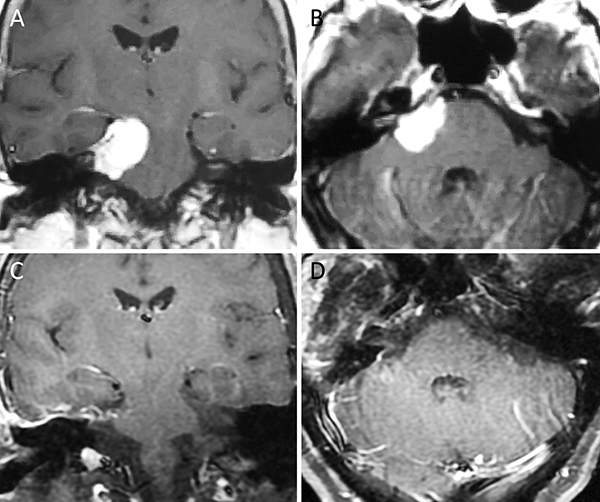

Figura 1. Meningioma tentorial medial. A-B: RM preoperatoria; C-D: RM postoperatoria.